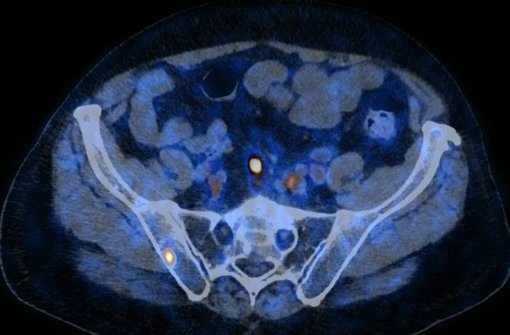

PSMA PET/CT (18F-PSMA)

Die PSMA PET/CT wird für die Beurteilung von Patienten mit einem Prostatakarzinom verwendet. Es handelt sich um eine Spezialuntersuchung die nur bei bestimmten Krankheitskonstellationen eingesetzt wird.

Nach der Ankunft in unserem Institut wird dem Patienten die schwach radioaktiv markierte Substanz (18F-PSMA) mittels einer Venenverweilkanüle in eine Armvene injiziert. Danach muss sich die Substanz im Körper verteilen. Nach 45-60 Minuten werden die PET/CT-Bilder angefertigt. Je nach Fragestellung ist es möglich, dass zusätzlich ein intravöses, iodhaltiges Röntgenkontrastmittel appliziert wird. Die Untersuchungsdauer auf dem Gerät beträgt zwischen 20 und 30 Minuten.